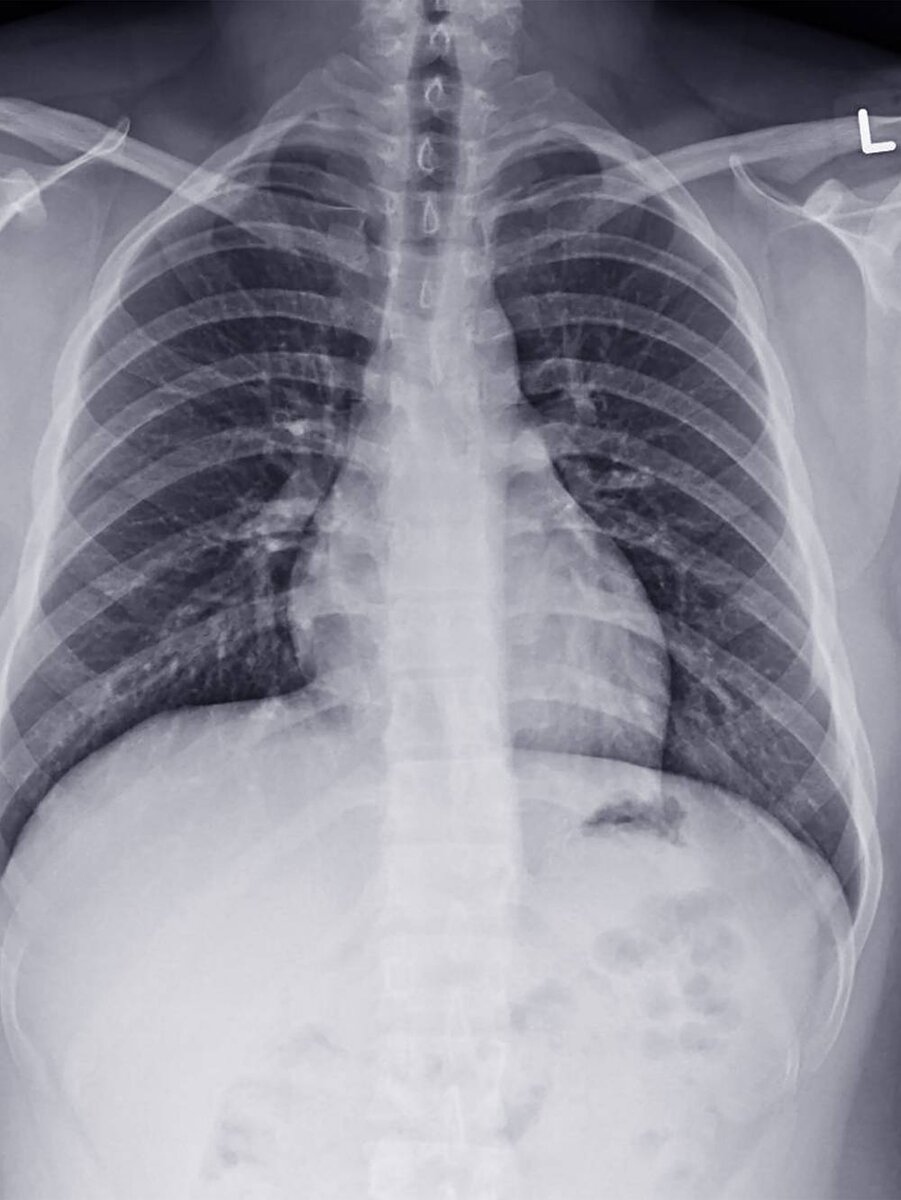

Флюорография — вариант рентгеновского исследования, который в основном используют для диагностики болезней легких.

Как и при обычном рентгене, во время флюорографии рентгеновские лучи проходят сквозь тело пациента. Мышцы и ребра задерживают некоторое количество рентгеновских лучей. Но легкие — это просто воздушные мешки, так что рентгеновское излучение они почти не поглощают.

В результате детекторы улавливают разницу и позволяют получить пленочную фотографию или цифровое изображение. Врачам удобнее работать с негативным вариантом снимка, на котором легкие выглядят темными, а кости и мышцы — более светлыми. Так лучше видно патологии.

Зачем нужна флюорография. Ее применяют для скрининга, то есть массового обследования бессимптомных людей, на туберкулез легких. Но на изображении могут быть заметны признаки и других заболеваний — например, пневмонии или сердечной недостаточности.

Чем флюорография отличается от рентгена. У изображения, полученного при помощи флюорографии, ниже разрешение, чем у рентгеновского изображения. Проще говоря, изображения легких, полученные при помощи флюорографии, получаются не такими четкими и информативными, как при рентгеновском исследовании.